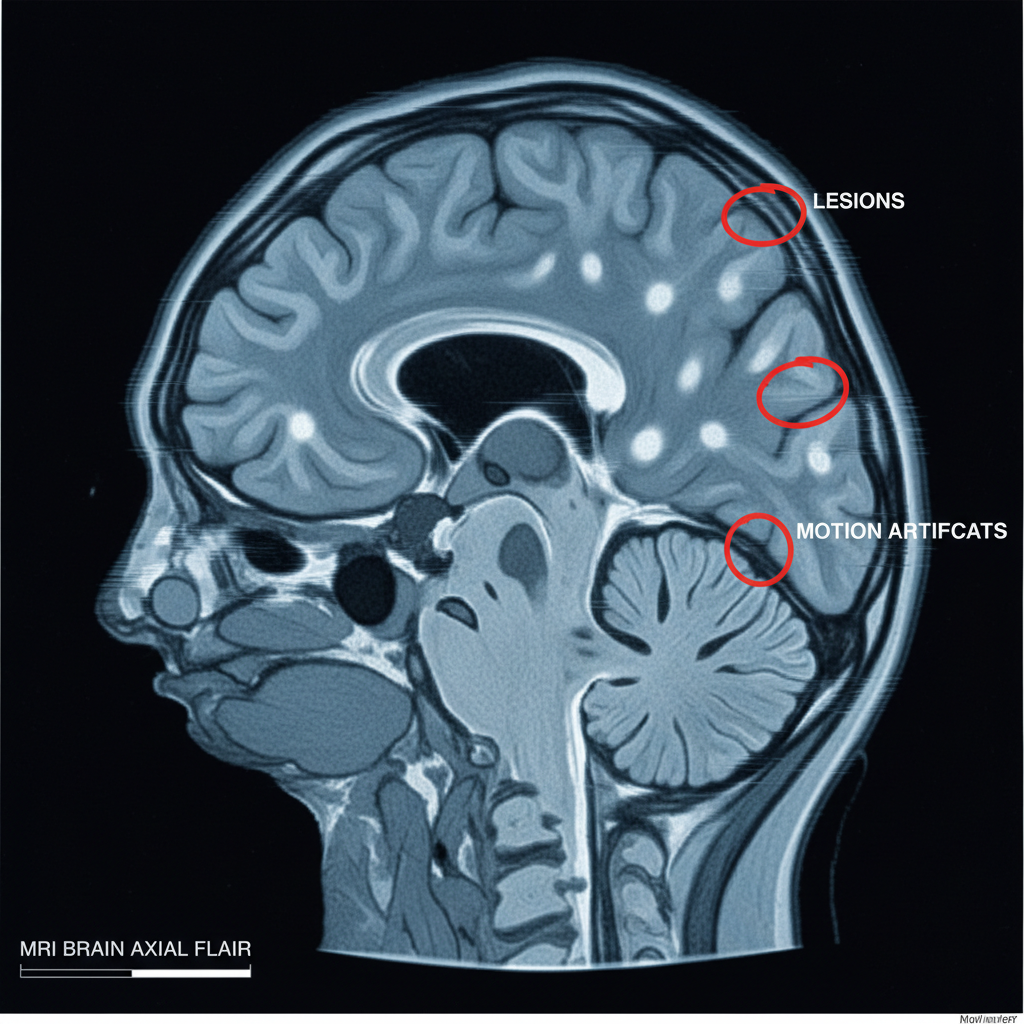

Obraz MRI z zaznaczonymi zmianami i artefaktami – przykłady sukcesów i błędów diagnostycznych

<!-- [Alt](/alt): Obraz MRI z zaznaczonymi zmianami i artefaktami – sukcesy i błędy diagnostyczne rezonansu magnetycznego -->

• Artefakt

Zakłócenie obrazu np. przez ruch pacjenta lub obecność metalu – potrafi całkowicie zafałszować wynik.

• Artefakt ruchowy

Zniekształcenie obrazu z powodu ruchu pacjenta.